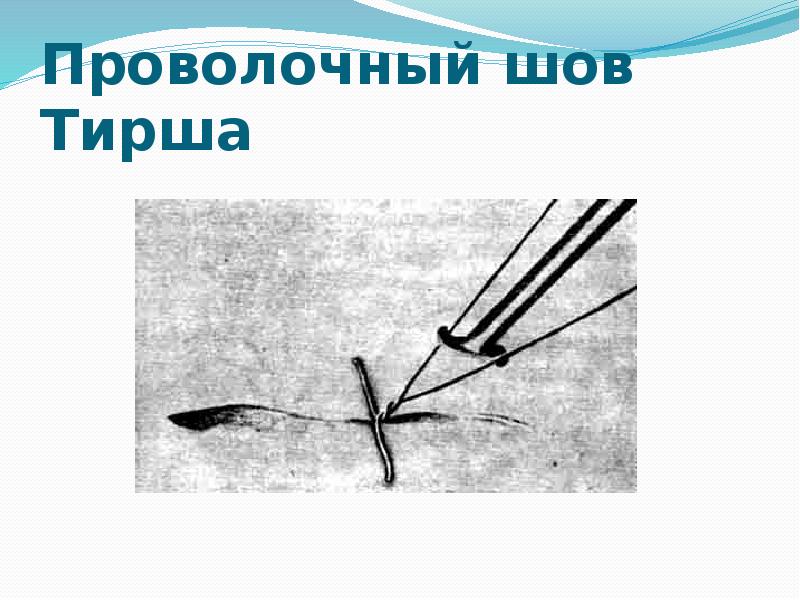

- 66. Проволочный шов Тирша

- 65. При внеочаговом соединении краев раны спицевым адаптационно-репозиционным аппаратом по С.Г. Измайлову (рис. 23)